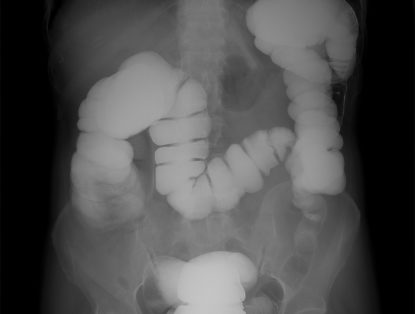

Fluoroscopy is a type of medical imaging that uses X-rays to obtain real-time images of the body’s internal structures. This procedure is ...

Read More